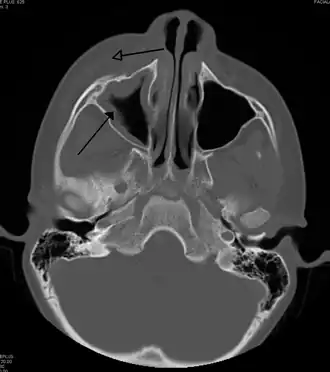

![]() Периорбитальный целлюлит, вызванный стоматологической инфекцией (которая также приводит к верхнечелюстному синуситу)) | |

Периорбитальный целлюлит, также известный как пресептальный целлюлит (но не следует путать с орбитальным целлюлитом, находящимся за перегородкой), — воспаление и заражение века и части кожи вокруг глаз[1] впереди орбитальной перегородки. Может быть вызван повреждением кожи вокруг глаз, и последующим распространением на веко; заражением носовых пазух вокруг носа (синусит); или распространением инфекции в другие места через кровь.

Периорбитальный целлюлит необходимо дифференцировать от орбитального целлюлита, который является чрезвычайной ситуацией и требует внутривенного введения (IV) антибиотиков. В отличие от орбитального целлюлита, у пациентов с периорбитальным целлюлитом отсутствуют выпуклые глаза (экзофтальм), ограниченное движение глаз (офтальмоплегия), боль при движении глаз, или потеря зрения. Если какой-либо из этих признаков присутствует, надо полагать, что пациент имеет орбитальный целлюлит и начать лечение IV антибиотиками. КТ-сканирование может быть сделано, чтобы очертить расширение инфекции.